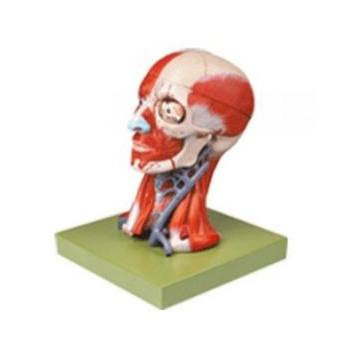

頭頸部肌肉、血管附腦模型 GD/A18211功能介紹■ 該模型由顱骨、頭頸部肌肉、腦正中矢狀切面、一側腦冠狀切面、大腦鐮、小腦、腦干、腦神經(jīng)以及眼和頸靜脈等10個部件組成,并顯示顱底、大腦半球、間腦、...